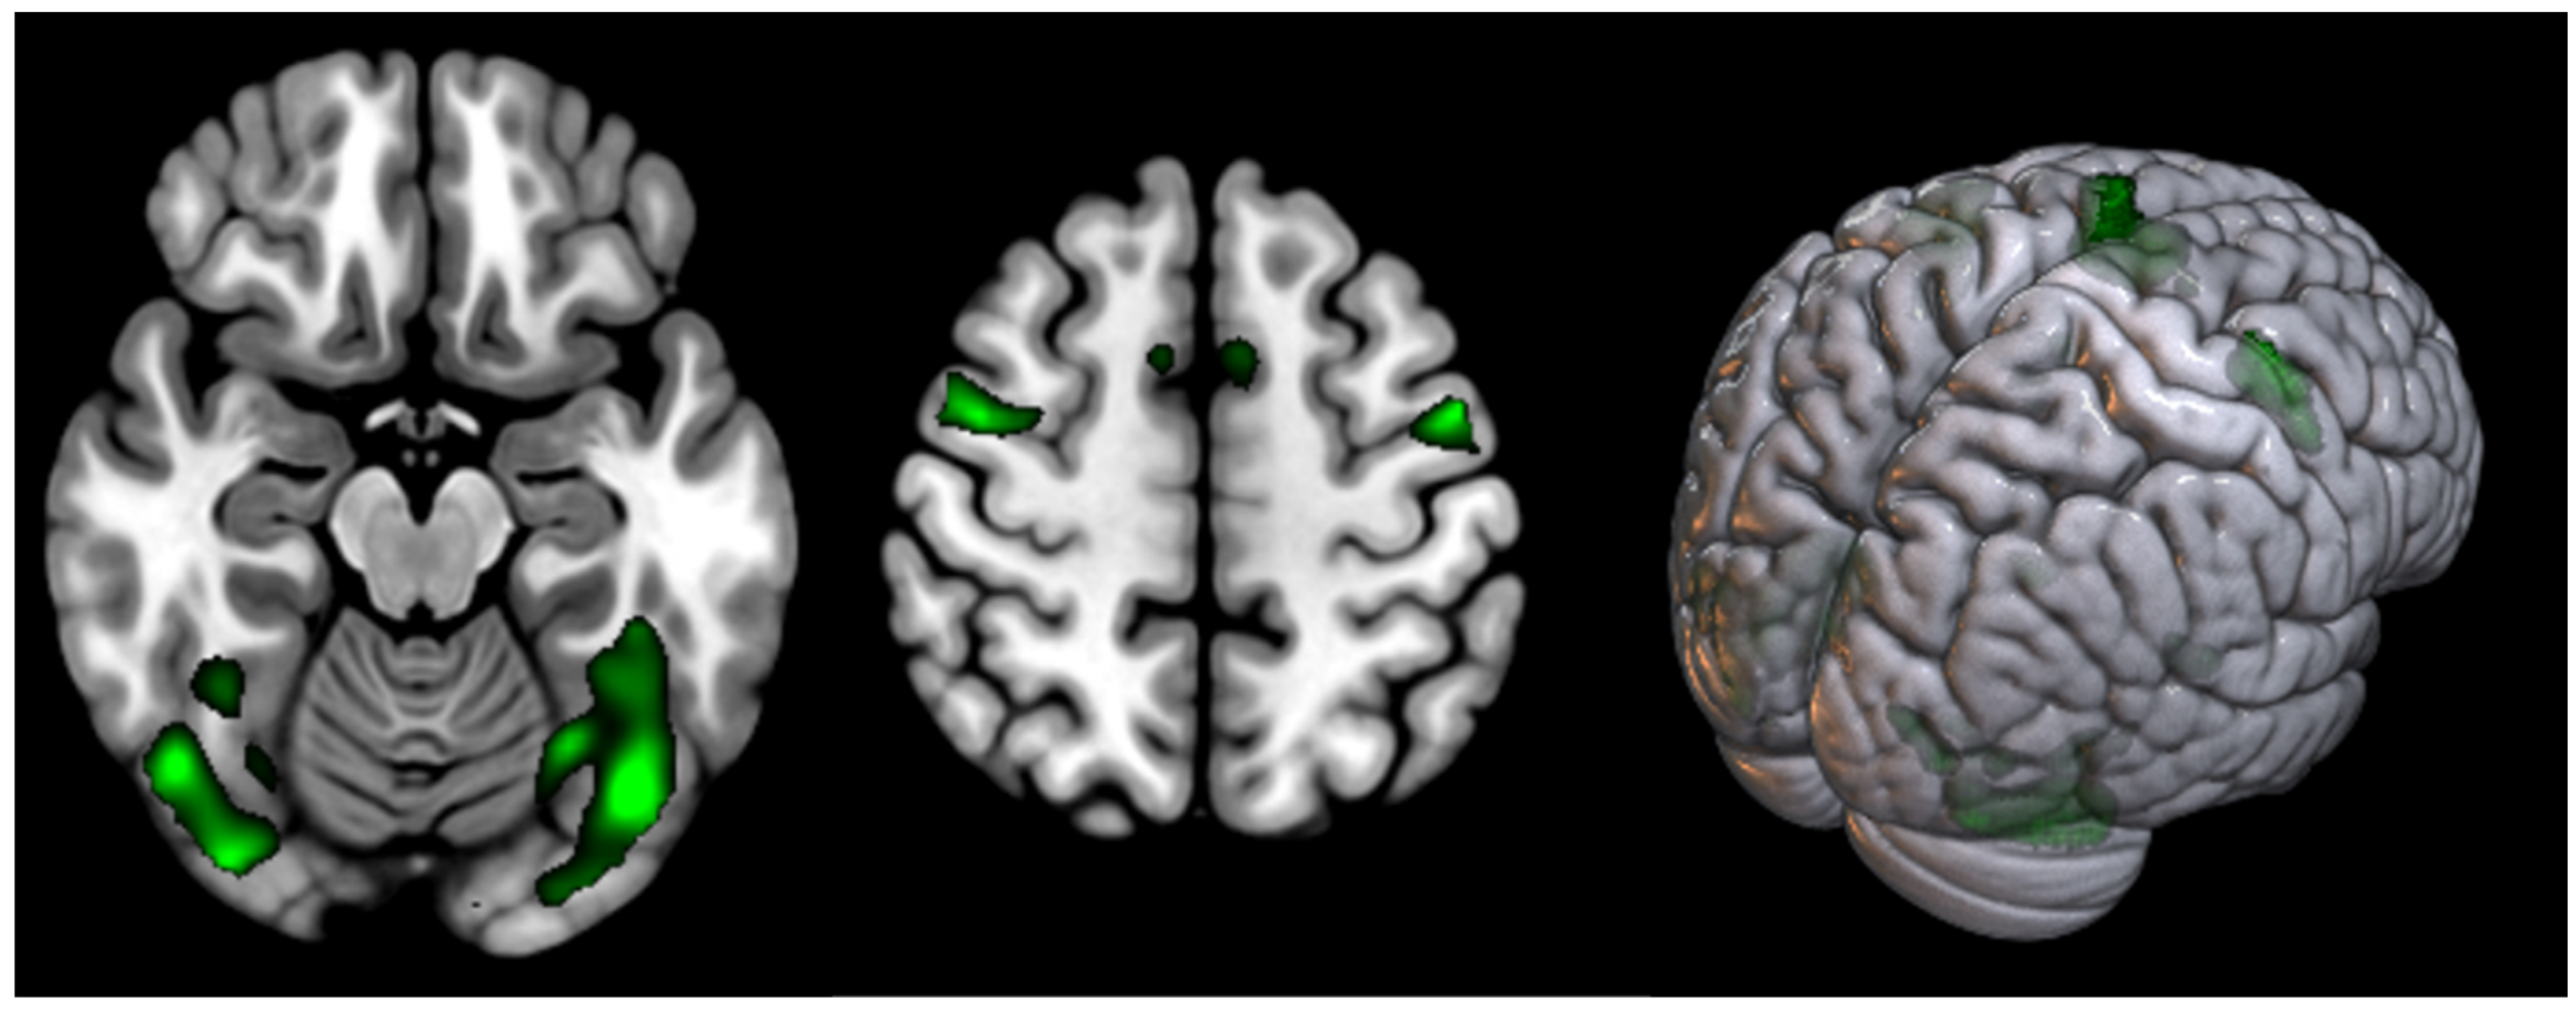

| T | PFWEcorr | Number of Voxels | Peak MNI Coordinate | |

|---|---|---|---|---|

| Supplementary motor cortex | 11.98 | <0.000 | 799 | 0 0 68 |

| Occipital cortex (Fusiform gyrus) (L) | 10.34 | <0.001 | 1507 | 60 8 30 |

| Occipital cortex (Fusiform gyrus) (R) | 9.24 | <0.005 | 706 | 44 −66 −20 |

| Precentral gyrus (L) (BA6) | <0.007 | 608 | −54 −2 48 | |

| Precentral gyrus (R) (BA6) | 8.67 | <0.009 | 221 | 42 −2 56 |